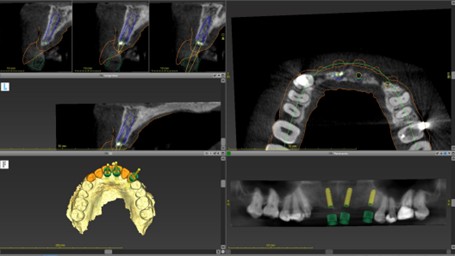

埋入シミュレーション

口腔内スキャナーで採得したデータとCT画像を融合させることで、インプラントの埋入位置・角度・深さを正確に誘導するマウスピース型の装置『サージカルガイド』を作製。

→口腔内スキャナーページへ

→サージカルガイドページへ

ガイドプロトコール